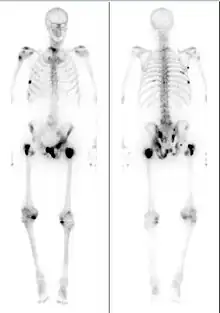

Bone scintigraphy scan of a man with metastatic prostate cancer. Dark spots indicate metastases along the pelvis, ribs, and shoulder.

For those with metastatic disease, the standard of care is androgen deprivation therapy, drugs that reduce levels of androgens (male sex hormones) that prostate cells require to grow.[51] Various drugs are used to lower androgen levels by blocking the synthesis or action of testosterone, the primary androgen. The first line of treatment is typically GnRH agonists like leuprolide, goserelin, or triptorelin by injection monthly or less frequently if needed.[52][51] GnRH agonists cause a brief rise in testosterone levels at treatment initiation, which can worsen disease in people with significant symptoms of metastases.[53] In these people, GnRH antagonists like degarelix or relugolix are given instead, and can also rapidly reduce testosterone levels.[53] Hormone therapy halts tumor growth in more than 95% of those treated,[54] and PSA levels return to normal in up to 70%.[55]